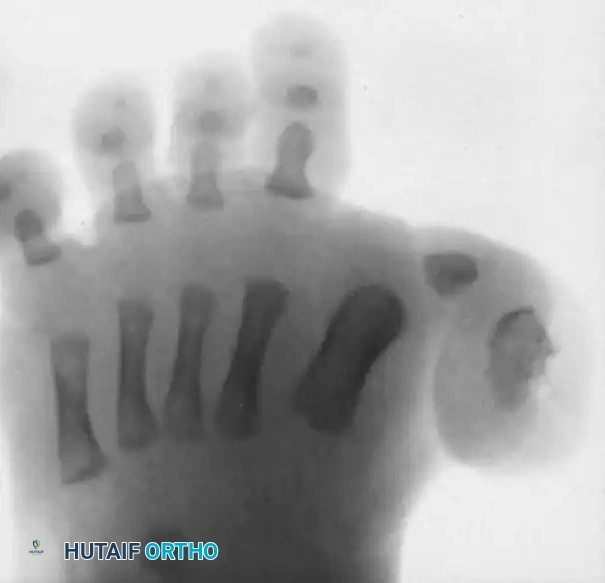

Radiographic Assessment

Standard weight-bearing (or simulated weight-bearing in infants) anteroposterior (AP), lateral, and oblique radiographs of the foot are mandatory.

Key Radiographic Findings:

* Medial subluxation or dislocation of the proximal phalanx on the first metatarsal head.

* A shortened and widened first metatarsal.

* Presence of accessory ossicles, delta phalanges, or rudimentary accessory digits medially.

* Evaluation of the intermetatarsal angle and the alignment of the lesser metatarsals.

Anteroposterior radiograph of a right foot with congenital hallux varus. Note the exceptionally short first metatarsal and the presence of an accessory distal phalanx acting as a medial tether.

Anteroposterior radiograph demonstrating the appearance after surgical correction. The medial tether has been excised, the MTP joint is centralized, and the alignment of the first ray is restored to a functional, neutral position.